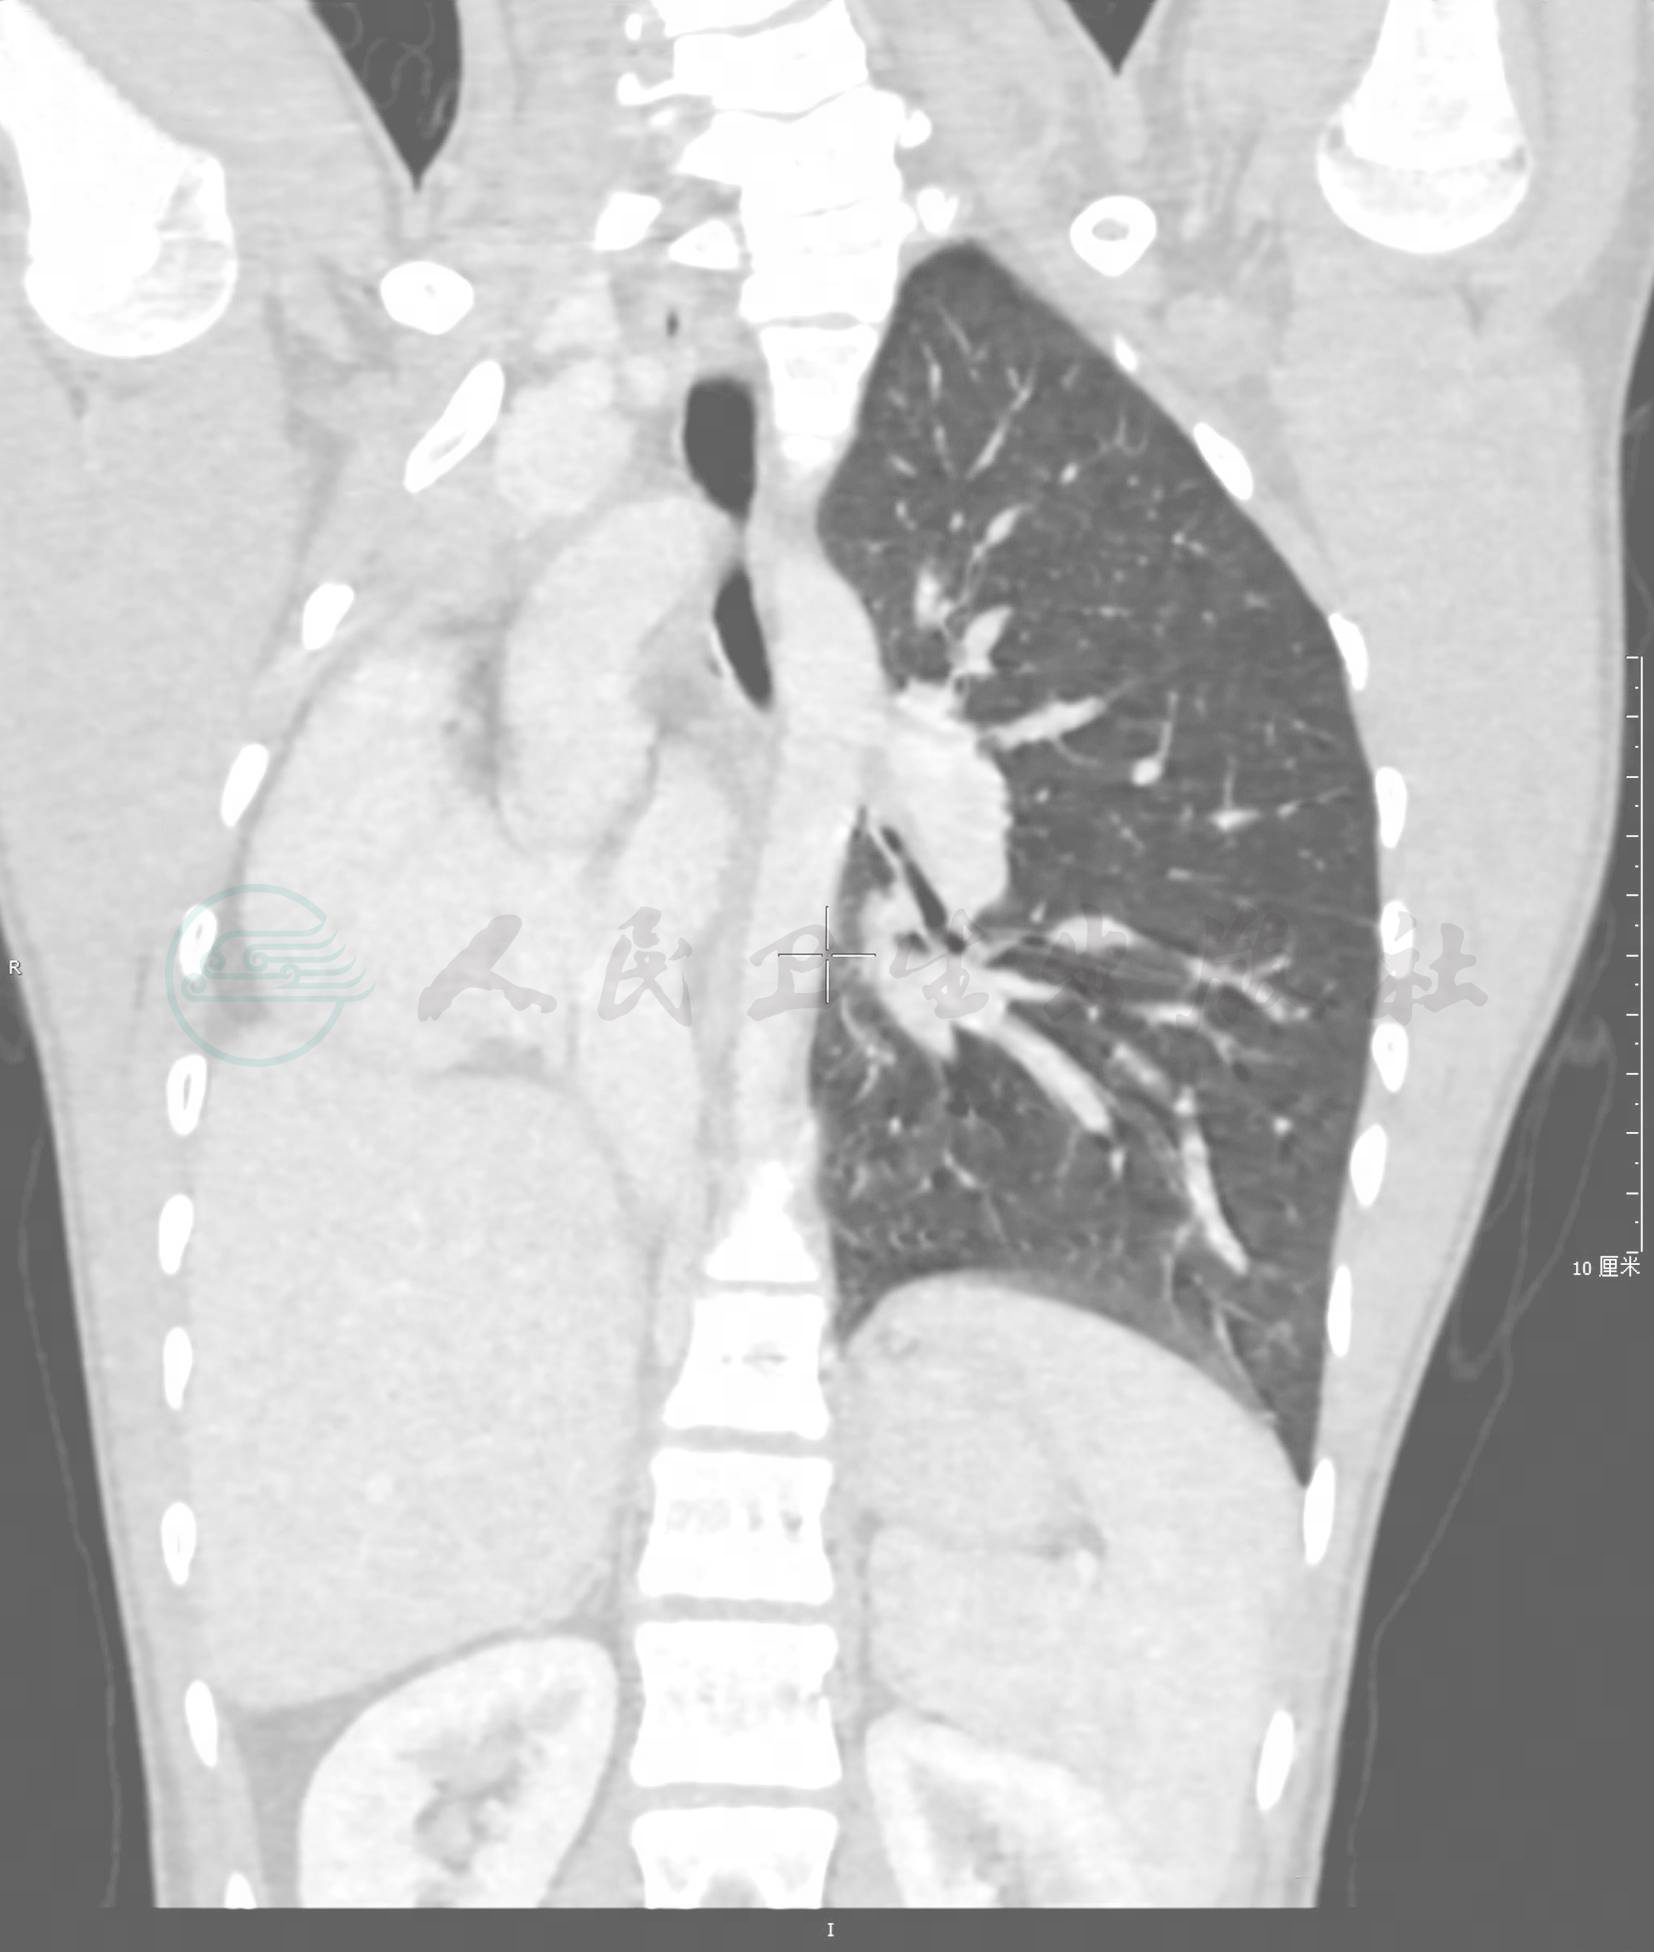

图1肺未发生

患儿男,15岁,以胸壁畸形就诊,右侧胸廓略小,右侧胸腔未见明确右肺组织,右侧肺动静脉均未见显示,右主支气管及分支未见显示,心影纵隔明显右移,心影不大,心脏旋转

引自:实用小儿呼吸病学(第2版).第2版.ISBN:978-7-117-29425-6.主编: